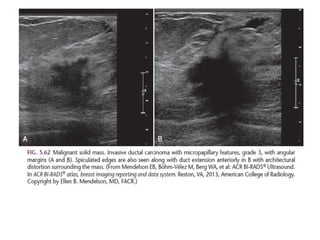

The shape of a mass is either round, oval or irregular.

The margin of a lesion can be:

Spiculated with radiating lines from the mass is a very suspicious finding.

Here a hyperdense mass with an irregular shape and a spiculated margin.

Notice the focal skin retraction.

This was reported as BI-RADS 5 and proved to be an invasive ductal

carcinoma.